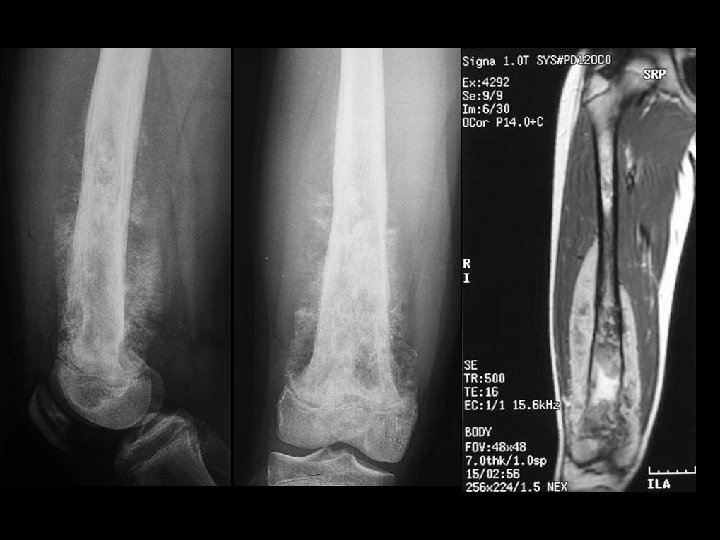

Osteosarcoma • Findings: – Aggressive lesion of the distal tibia in a skeletally immature person – “cloud-like” appearance = calcified osteoid matrix – Intense periosteal reaction – Soft tissue mass • ddx: – NONE! – This is an Aunt Minnie!